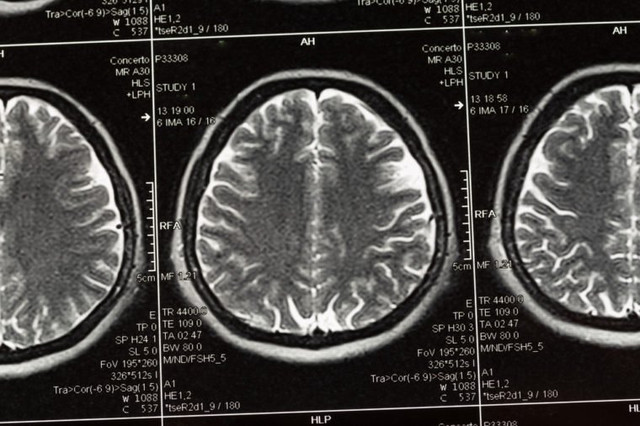

"Chuyện ấy" kích thích sản sinh ra hormone oxytocin khiến bạn cảm thấy gắn kết với nửa kia và hormone dopamine tăng hoạt động của hệ thần kinh tưởng tượng ở não bộ. Kết quả là bạn thấy thỏa mãn và gần gũi với đối tác của mình.